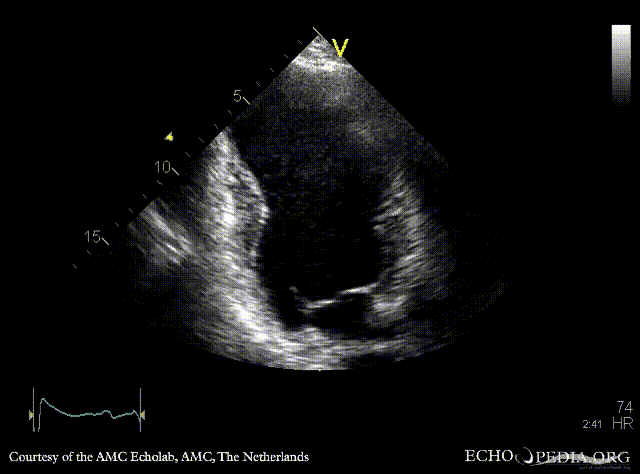

A2CH